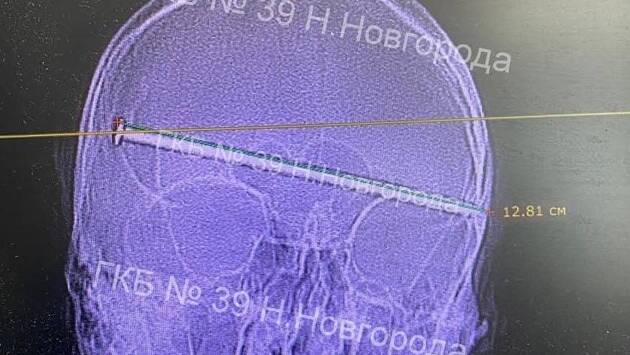

Огромный гвоздь размером 12 сантиметров насквозь проткнул череп мужчины в Нижнем Новгороде. Его спасли врачи, сообщается на странице городской клинической больницы №39 во «ВКонтакте».

Как уточнили медики, врачи более трех часов проводили операцию, в ходе которой им удалось извлечь гвоздь из головы пациента. Медицинское вмешательство проводили заведующий нейрохирургическим отделением Александр Лавренюк и врач Павел Смирнов.